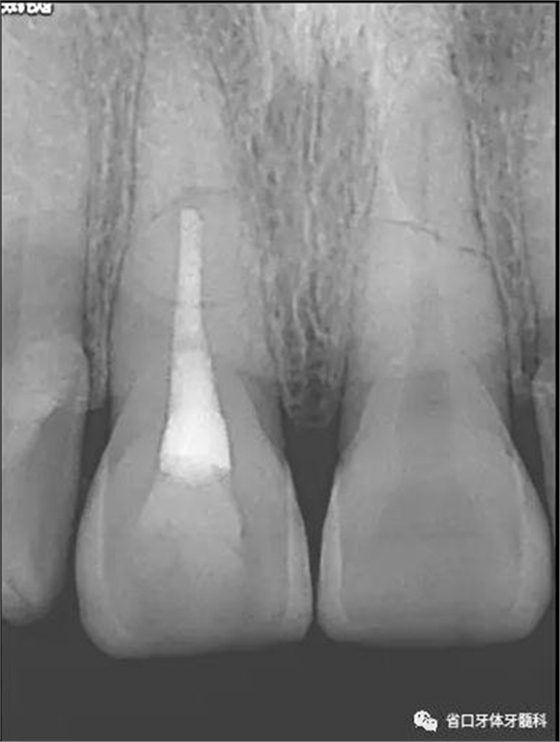

X線片:11、21根中段見橫行根折線,無移位,根尖無明顯異常。

圖2 術(shù)前根尖片

圖7 熱牙膠根充片